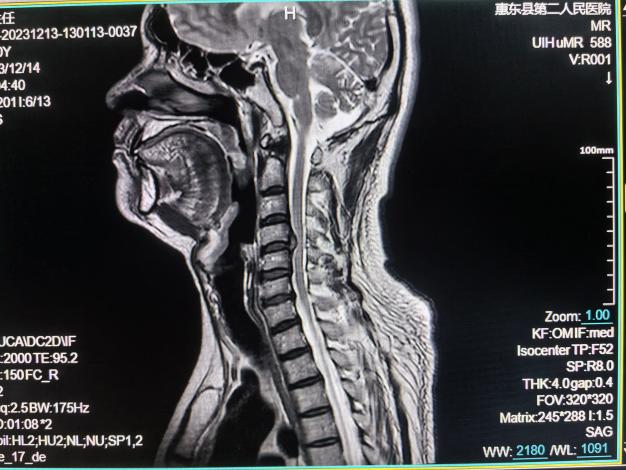

脊柱MRI检查

椎管内肿瘤:包括髓内、外肿瘤、硬膜下肿瘤、硬膜外肿瘤;脊膜膨出和脊髓脊膜膨出;脊髓创伤;硬膜外脓肿和硬膜下脓肿;椎管内血管畸形;脊髓空洞症;脊髓萎缩;⑧椎间盘突出;⑨椎管狭窄。